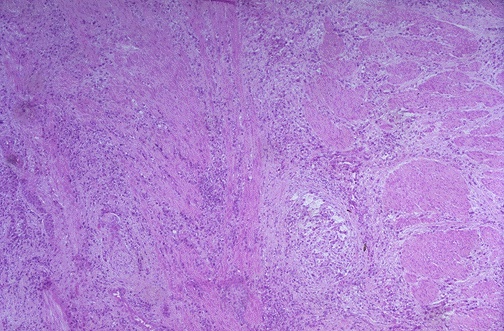

Image 4.3

The low power microscopic appearance of the diffusely thickened, leather-like stomach at autopsy is seen here.